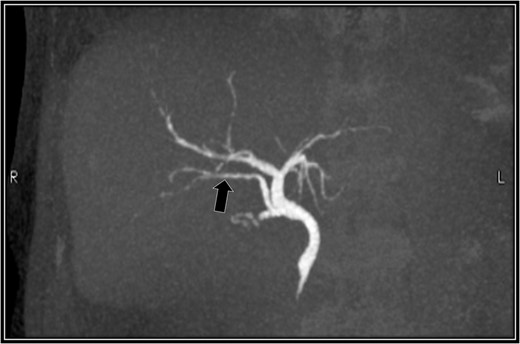

The patient was placed in supine position. Initially, intracorporeal procedures were performed in the laparoscopic view through four trocars (one 12-mm port and three 5-mm ports). We considered using intraoperative cholangiography to explore the right accessory hepatic duct. We incised the serosa by the neck of the gallbladder, used the Rouviere sulcus as a landmark, and peeled off the Calot triangle near the gallbladder. Subsequently, we identified the cystic artery and isolated it. Then we identified the cystic duct, and we inserted a cholangiography tube into it. The intraoperative cholangiography image showed that the right accessory hepatic duct branching from the cystic duct dominated an anterior segment of the right hepatic lobe (Fig. 3). Next, we isolated the cystic duct while preserving the right accessory hepatic duct. We resected the gallbladder. The total operating time was 125 min, and the intraoperative blood loss was minimal. Since the patient's postoperative course was uneventful, he was discharged 4 days later. We performed drip-infusion cholangiography-CT (DIC-CT) 48 days postoperatively. The DIC-CT scan demonstrated that the right accessory hepatic duct was intact, and it dominated an anterior segment of the right hepatic lobe (Fig. 4).

Drip-infusion cholangiography-computed tomography scan. Forty-eight days postoperatively, the right accessory hepatic duct is intact (black arrow), and it dominates an anterior segment of the right hepatic lobe, as indicated by the intraoperative cholangiography scan.